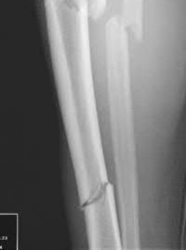

Figures A and B demonstrate a distal third tibial shaft fracture with simple intra-articular extension. The axial and coronal CT cuts in Figures C and D further clarify the articular injury. Illustrations A and B demonstrate a comminuted distal third tibial fracture with simple intra-articular extension. Illustrations C and D are fluoroscopic images of the same injury after intramedullary nailing and percutaneous fixation of the articular component.